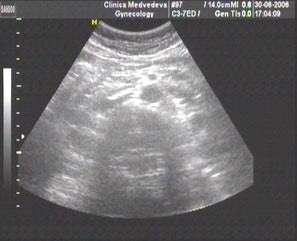

Сходила на узи! Сказала все отлично! Главное отпустить навязчивую идею...

@tamara27, нет) это просто картинка) а мы пока что планируем) вот и ездила узнать зреют ли фолликулы) есть и доминант)